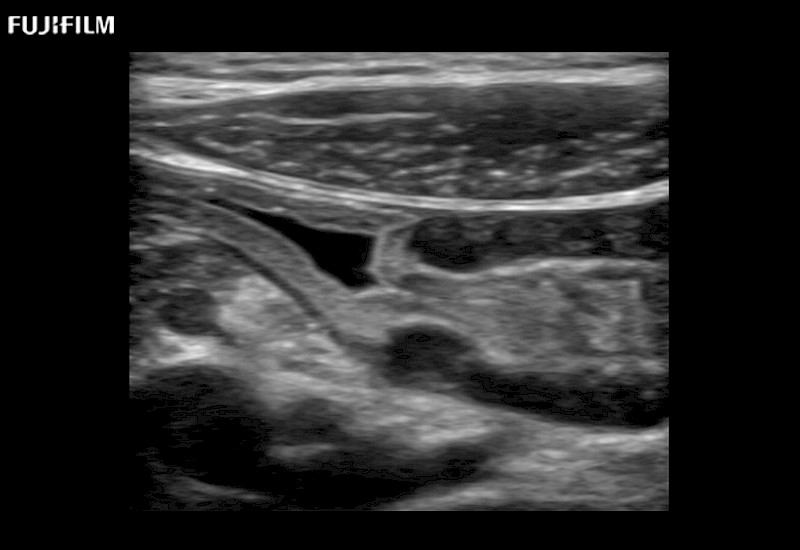

Extraordinary high-resolution digital imaging

- Exceptional near and far-field resolution

- Instant feedback on tumor margin delineation

- Valuable information to guide tumor resections

- Exceptional near and far-field resolution

- Instant feedback on tumor margin delineation

- Exceptional near and far-field resolution

- Exceptional near and far-field resolution

- Instant feedback on tumor margin delineation

- Exceptional near and far-field resolution

- Instant feedback on tumor margin delineation

- Exceptional near and far-field resolution

- Instant feedback on tumor margin delineation

- Exceptional near and far-field resolution

- Instant feedback on tumor margin delineation

- Valuable information to guide tumor resections

- Exceptional near and far-field resolution

- Instant feedback on tumor margin delineation

- Valuable information to guide tumor resections

- Exceptional near and far field resolution

- Instant feedback on tumor margin delineation

- Valuable information to guide tumor resections

- Exceptional near and far-field resolution

- Instant feedback on tumor margin delineation

- Valuable information to guide tumor resections

- Exceptional near and far field resolution

- Instant feedback on tumor margin delineation